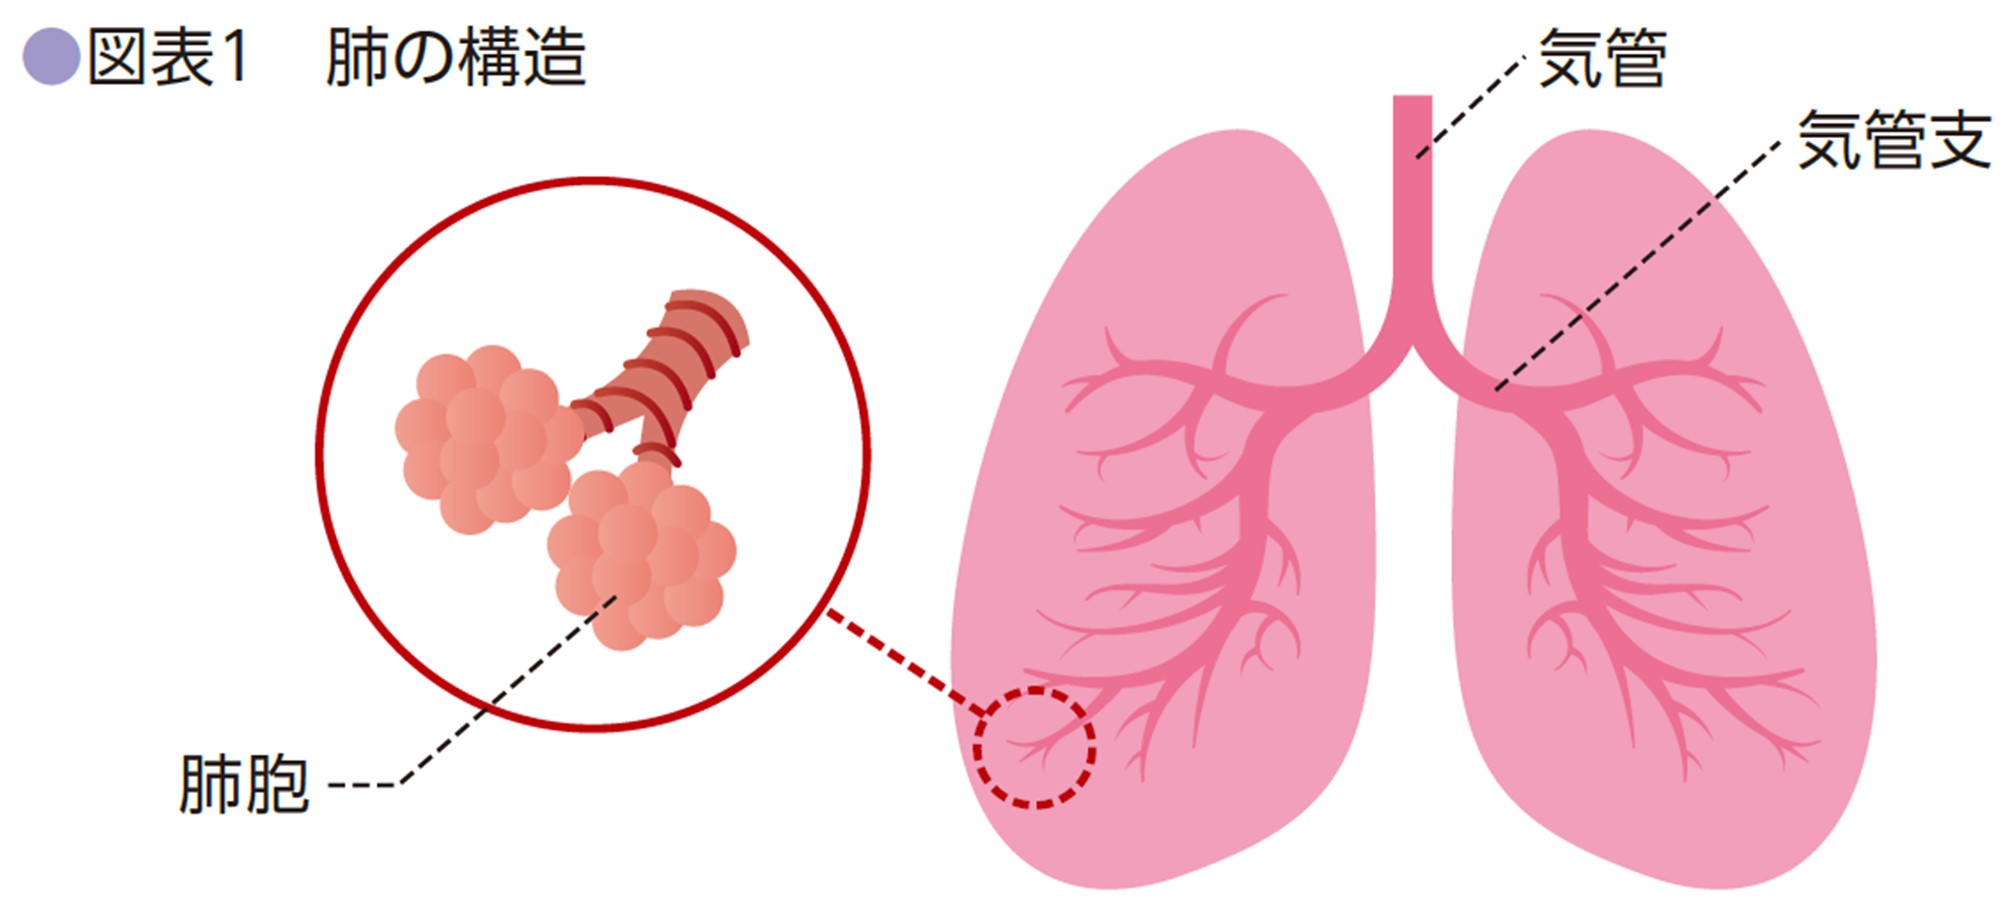

- T は原発腫瘍のサイズおよびその他の特徴を示します。

- N は、がんがリンパ節に到達しているかどうかを示します。

- M は、がんが体の他の部分に転移または拡散しているかどうかを示します。

- 腫瘍は 2 本の主気管支 (気道) の 1 つに成長していますが、気管分岐部 (気管支を分割する軟骨) から少なくとも 2 cm 離れています。腫瘍の大きさは4cm以下です。

- 腫瘍は肺を覆う膜である内臓胸膜まで増殖しました。腫瘍の大きさは4cm以下です。

- 腫瘍は気道を部分的に閉塞していますが、大きさは 4 cm 以下です。